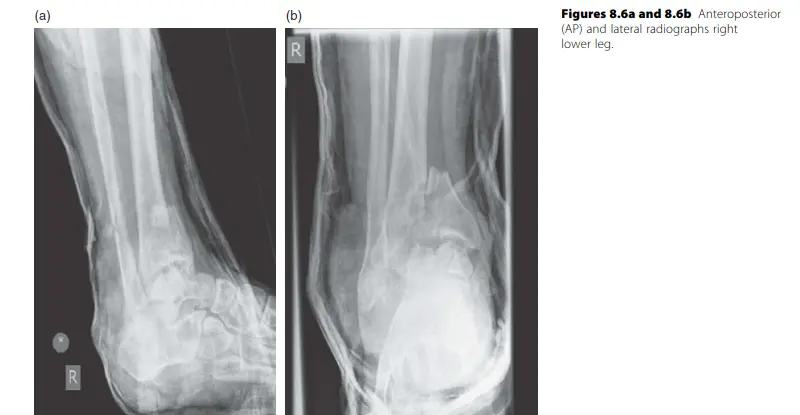

- الأشعة السينية (X-rays): هي الخطوة الأولى والأساسية لتشخيص معظم الكسور والخلوع. يتم أخذ صور من زوايا مختلفة (أمامية، جانبية، ومائلة) لتقييم موقع الكسر ونمطه ودرجة إزاحته.

- التصوير المقطعي المحوسب (CT Scan): يُعد المعيار الذهبي لتقييم الكسور المعقدة، خاصة تلك التي تمتد إلى المفاصل (مثل كسور الهضبة الظنبوبية، كسور البيلون، كسور الحوض، كسور الكاحل، وكسور عظام القدم). يوفر صورًا ثلاثية الأبعاد تفصيلية تساعد في التخطيط الجراحي الدقيق، وتقييم الاستدارة في كسور قصبة الساق.